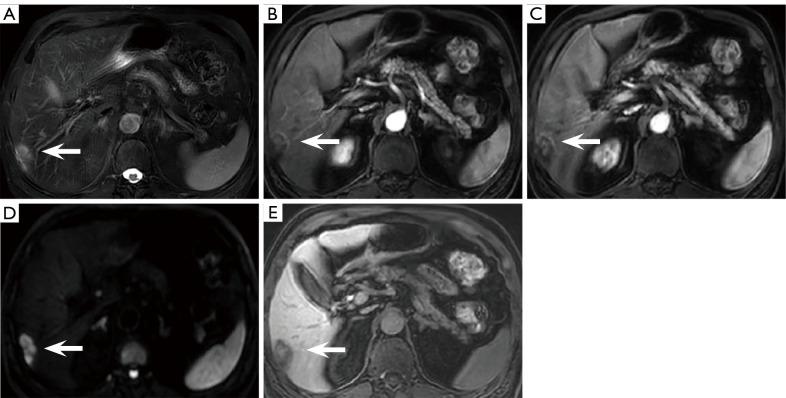

钆塞酸二钠(Gd-EOB-DTPA)增强简化磁共振成像(MRI)用于高危患者肝细胞癌监测:一项中国多中心研究

Given the limited capacity and suboptimal sensitivity of ultrasonography (US), gadoxetic acid disodium (Gd-EOB-DTPA)-enhanced magnetic resonance imaging (MRI) demonstrates good diagnostic performance for hepatocellular carcinoma (HCC). Some researchers have proposed that the abbreviated MRI (AMRI) protocols have potential as a surveillance tool. However, few studies have compared multiple AMRI protocols with complete Gd-EOB-DTPA contrast-enhanced MRI for HCC surveillance. We aimed to explore and compare the diagnostic performance of 3 AMRI protocols as HCC surveillance in high-risk patients.

METHODS

This multi-center, retrospective, blinded reader study conducted in China consecutively enrolled 339 patients with hepatitis and/or cirrhosis who underwent complete Gd-EOB-DTPA contrast-enhanced MRI for HCC surveillance from 2020 to 2023. We extracted 3 additional AMRI protocols: noncontrast-AMRI [NC-AMRI: T2-weighted imaging (T2WI) and diffusion-weighted imaging (DWI)]; dynamic-AMRI (Dyn-AMRI: early and late arterial phases, portal venous phase, and DWI); and hepatobiliary phase-AMRI (HBP-AMRI: T2WI, DWI, and HBP). Then, 2 independent radiologists assessed the AMRI and complete Gd-EOB-DTPA contrast-enhanced MRI protocols. Patients were classified as HCC positive/HCC negative based on the reference standard. Agreement was assessed using Kappa statistics. The acquisition time differences of the 4 MRI protocols were analyzed by analysis of variance (ANOVA). Per-lesion HCC diagnostic performances were compared by Cochran's Q test. Receiver operating characteristic (ROC) curves for the 3 AMRI protocols were evaluated, and the area under the ROC curve (AUROC) was calculated and compared by DeLong's test.

RESULTS

A total of 353 lesions were detected in the 339 included patients, and 21/339 patients were diagnosed with HCC (prevalence, 6.2%). The inter-observer agreement was good for all 4 MRI protocols (k>0.75). Acquisition times differed significantly (P<0.001), from the shortest to the longest: NC-AMRI (263.44±5.05 s) < HBP-AMRI (269.18±4.93 s) < Dyn-AMRI (307.71±4.93 s) < complete Gd-EOB-DTPA contrast-enhanced MRI (582.03±3.59 s). The sensitivity (Cochran's Q=14.667, P=0.002) and specificity (Cochran's Q=59.682, P<0.001) of 4 MRI protocols were statistically significant. HBP-AMRI showed the highest sensitivity (84.00%), whereas Dyn-AMRI exhibited the highest specificity (99.39%) among 3 AMRI protocols. The per-lesion positive predictive value (PPV) for the NC-AMRI, Dyn-AMRI, and HBP-AMRI was 41.66%, 88.89%, and 47.72%, the corresponding negative predictive value (NPV) was 96.21%, 97.31%, and 98.70%, and the number needed to diagnose (NND) for the NC-AMRI, Dyn-AMRI, HBP-AMRI, and complete Gd-EOB-DTPA contrast-enhanced MRI was: 1.865, 1.577, 1.234, and 1.569, respectively. DeLong's test showed the AUROC value of either Dyn-AMRI or HBP-AMRI was significantly higher than that of NC-AMRI (Z=2.330, P=0.019; Z=2.680, P=0.007, respectively), but no significant difference between HBP-AMRI and Dyn-AMRI (Z=1.643, P=0.100).

CONCLUSIONS

AMRI protocols can be implemented in clinical practice as a patient-centered and tailored regimen for HCC surveillance in China. NC-AMRI might become an optional tool due to its minimal scanning time, lower cost, and exemption from contrast agents. Dyn-AMRI, achieving the highest specificity, is a reliable surveillance strategy. HBP-AMRI as a favorable alternative showed a high sensitivity and NPV while maintaining considerable specificity and NND.